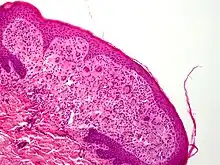

Xanthogranuloma iuvenile (Xanthogranulome juvénile[1]) (10x) vu en coupe